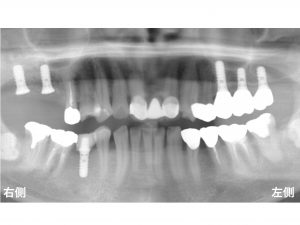

以下が手術直後です。

上顎洞内部には、

人工の骨が入っています。

以下は、

インプラントを埋め込んだ直後です。

この時点で、

上顎左側のインプラント部分は、しっかりと噛めるようになっています。

以下は治療後です。

患者様は、

これでしっかりと噛めるようになりました。